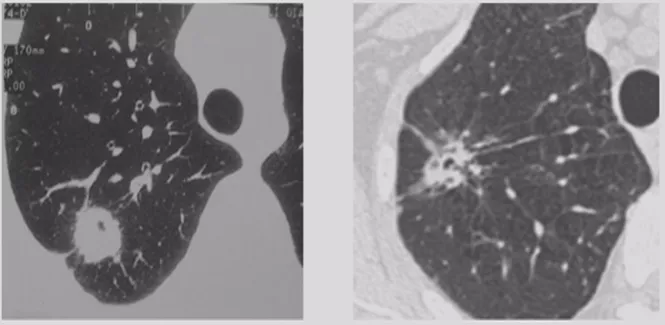

CT随访

1)病灶大小无变化、实性成分增多

这个结节大小没有太大变化,实性成分增多,这不是一个好征象,可以考虑手术。

2)病灶缩小、出现实性成分

容易被大家忽略的是结节的大小变小,但实性成分增多,值得大家重视。不要认为结节变小了就一定是良性。